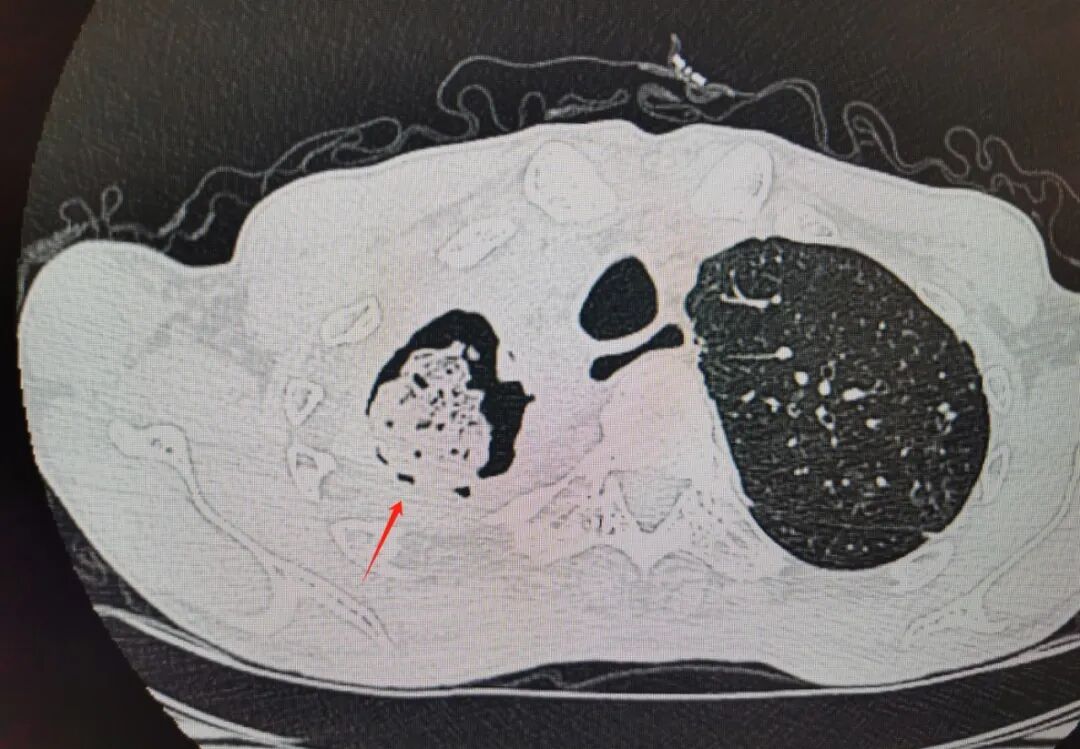

患者胸部CT影像资料

经肺科医生诊断,患者患有肺结核合并曲霉感染,其右肺上叶已被结核菌严重“蛀损”,形成巨大空洞,肺部组织破坏严重,肺功能严重受损。因随时面临咯血窒息风险,他被转入重症医学科(ICU)接受监护治疗。在住院期间,患者多次咯血,出血量高达1200ml(接近一个成年人全身近1/4的血液),每一次咯血都像是在鬼门关前徘徊,但医护人员凭借着快速、积极的抢救,一次又一次将他从死亡线上拉了回来。